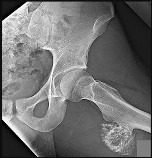

Question 1

A 12-year-old obese male presents with left thigh pain and obligatory external rotation during hip flexion.

What is the most widely accepted absolute indication for prophylactic in situ pinning of the asymptomatic contralateral hip in the setting of Slipped Capital Femoral Epiphysis (SCFE)?

Explanation

While the decision to prophylactically pin the contralateral hip in SCFE is often debated, absolute indications generally include patients with a known endocrinopathy (such as hypothyroidism or growth hormone deficiency) or renal osteodystrophy, as they have a significantly higher risk of a sequential slip. Other relative indications include young age (e.g., modified Oxford bone age < 16) or an inability to follow up, but endocrine disorders represent the most universally accepted absolute indication.